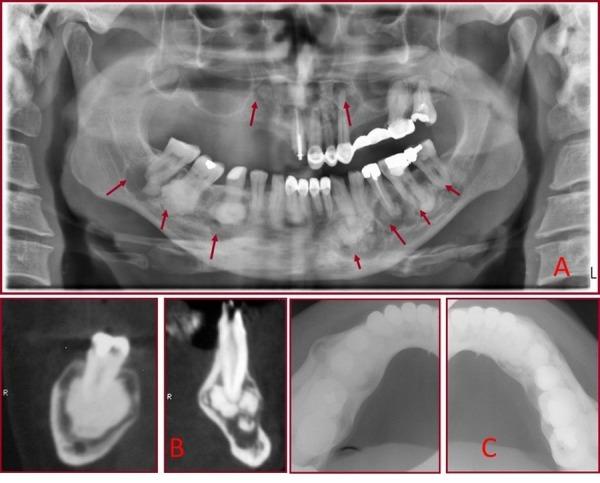

Florid cemento-osseous dysplasia (FCOD) has been described as a condition that characteristically affects the jaws of middle-aged black women. This condition has also been classified as gigantiform cementoma, chronic sclerosing osteomyelitis, sclerosing osteitis, multiple estenosis and sclerotic cemental masses. It usually exhibits as multiple radiopaque cementum-like masses distributed throughout the jaws. Radiographically, FCOD appears as dense, lobulated masses, often symmetrically located in various regions of the jaws. Computed tomography, because of its ability to give axial, sagittal, and frontal views, is useful in the evaluation of these lesions. This article reports the case of a 45-year-old white man who was diagnosed with FCOD on the basis of clinical, radiographic, biochemical and histological findings. It is of major importance to realize that all dentists have a unique opportunity as well as ethical obligation to assist in the struggle against wrong dental treatments that might save patients dental health. This case report illustrates the point that periapical radiolucencies may represent benign fibro-osseous lesions that may be overlooked or result in unnecessary endodontic treatment. Key words:Florid cemento-osseous dysplasia, florid osseous dysplasia, fibro-osseous lesions.

florid骨化性纤维瘤(FCOD)被描述为一种典型影响中年黑人女性颌骨的病症。这种病症也被归类为巨大型牙骨质瘤、慢性硬化性骨髓炎、硬化性骨炎、多发性狭窄和硬化性牙骨质团块。它通常表现为分布于整个颌骨的多个不透射线的牙骨质样团块。在影像学上,FCOD表现为致密的、分叶状团块,常对称位于颌骨的各个区域。计算机断层扫描因其能够提供轴向、矢状和额状视图,在评估这些病变时很有用。本文报告了一例45岁白人男性病例,该患者根据临床、影像学、生化和组织学检查结果被诊断为FCOD。重要的是要认识到,所有牙医都有独特的机会以及道德义务,协助对抗可能损害患者牙齿健康的不当牙科治疗。本病例报告说明了根尖周透射区可能代表良性纤维-骨病变,这些病变可能被忽视或导致不必要的牙髓治疗这一点。关键词: florid骨化性纤维瘤, florid骨发育异常,纤维-骨病变